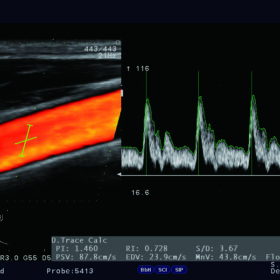

Ultrasound Aloka Prosound F37 – Image Gallery and Videos

Cardio 2D, Color, PW and TDI mode